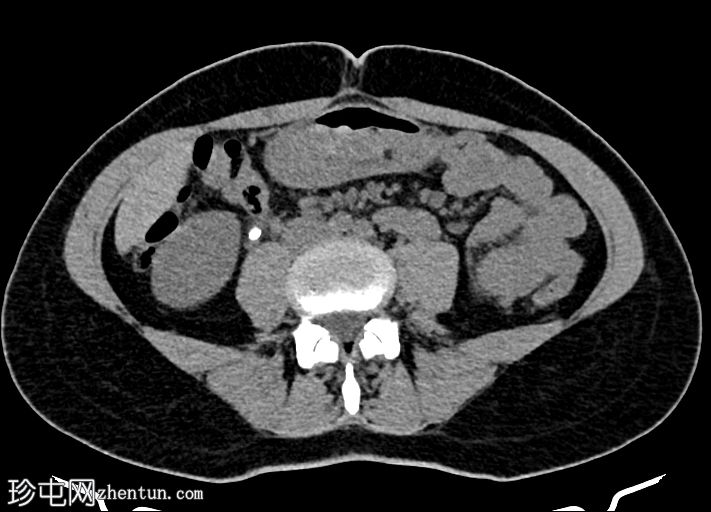

轴位肾部

排泄期

右侧输尿管上段可见一小块高密度结石(约1500 HU)

近端输尿管及右侧肾盂肾盏系统中度扩张

右髂窝内可见多个小钙化结节,符合钙化淋巴结的特征